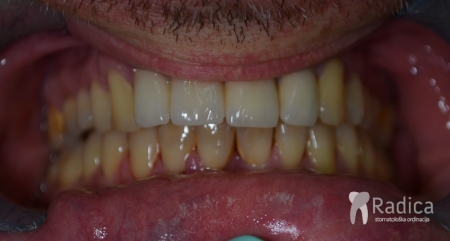

U sljedećem primjeru je fiksna ortodontska terapija rađena samo u donjoj čeljusti. Nakon toga su napravljeni novi protetski radovi u gornjoj i donjoj čeljusti – rad dr. Gorana Radice.

Na sljedećoj slici se mogu vidjeti početak i kraj ortodontske i protetske terapije. Protetske radove radio je dr. Goran Radica.